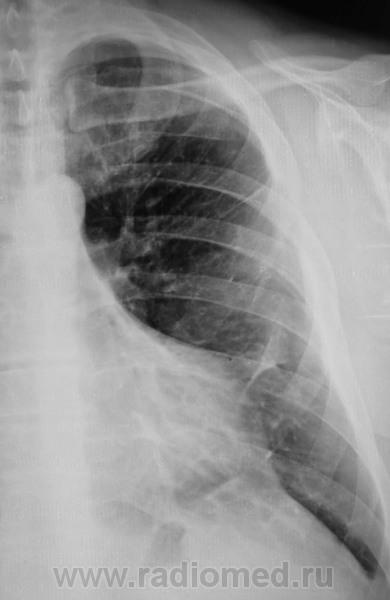

Понял, а не допускаете мысли, что могла быть операция на лёгком с резекцией ребра ( хорошо виден фрагмент заднего отрезка V ребра слева, с абсолютно нормальной костной структурой, что нехарактерно для метастатического поражения ребра ).

Коллеги, не вижу V ребра слева ( это мне подсказал, коллега который просматривает сайт). Как это расценивать?

Ребра не видно. Передайте коллеге, что он прав.

Вот так изолировано, да элегантно по одному ребру шарахнуло?